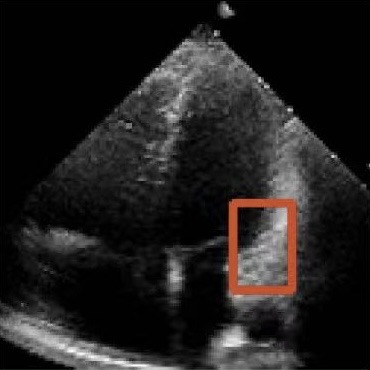

Our work has some limitations. While the model performs well in ultrasound cardiac video segmentation, its full potential in other medical video object segmentation scenarios remains to be explored. This includes testing on fully-supervised and semi-supervised benchmarks, which would allow us to evaluate the model’s performance in accurately modeling long-term temporal sequences. Future work could also focus on developing metrics that better assess the temporal consistency of sequences. Figure 10 shows that the model sometimes over-relies on its own predictions during the final optimization stage. For some difficult samples, this hinders the precise delineation of contours. A potential direction is to develop more flexible boundary definitions or adaptive corrections to address these artifacts. Our current intermediate state matrix is not a standard square matrix, which restricts chunkwise parallelization and hardware acceleration. Future work could explore a square matrix design to enable more efficient parallel operators, reduce training time, and improve inference speed.

Refer to caption

Figure 10: Failure cases on CAMUS (a-c) and EchoNet-Dynamic (d-f) test sets.